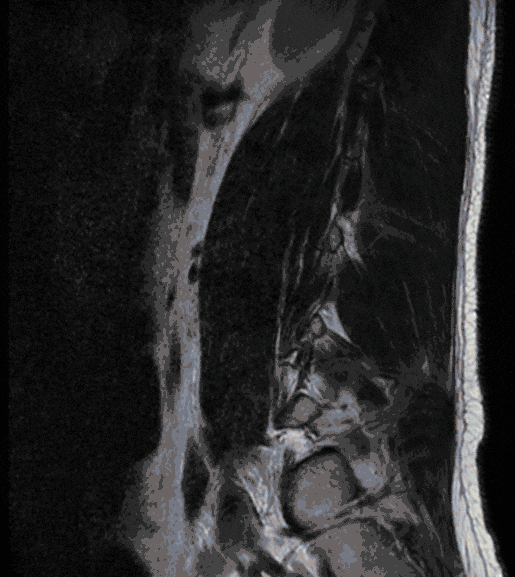

Gelenkzysten

Gelenkzysten treten meist in Folge einer degenerativen Erkrankung der Wirbelgelenke (Facetten-Gelenke) auf und können Ausdruck einer Instabilität sein. Da Gelenkzysten zu einer deutlichen Einengung des Wirbelkanals führen können, können sie mit Beschwerden einhergehen, die einer Spinalkanalstenose gleichen.